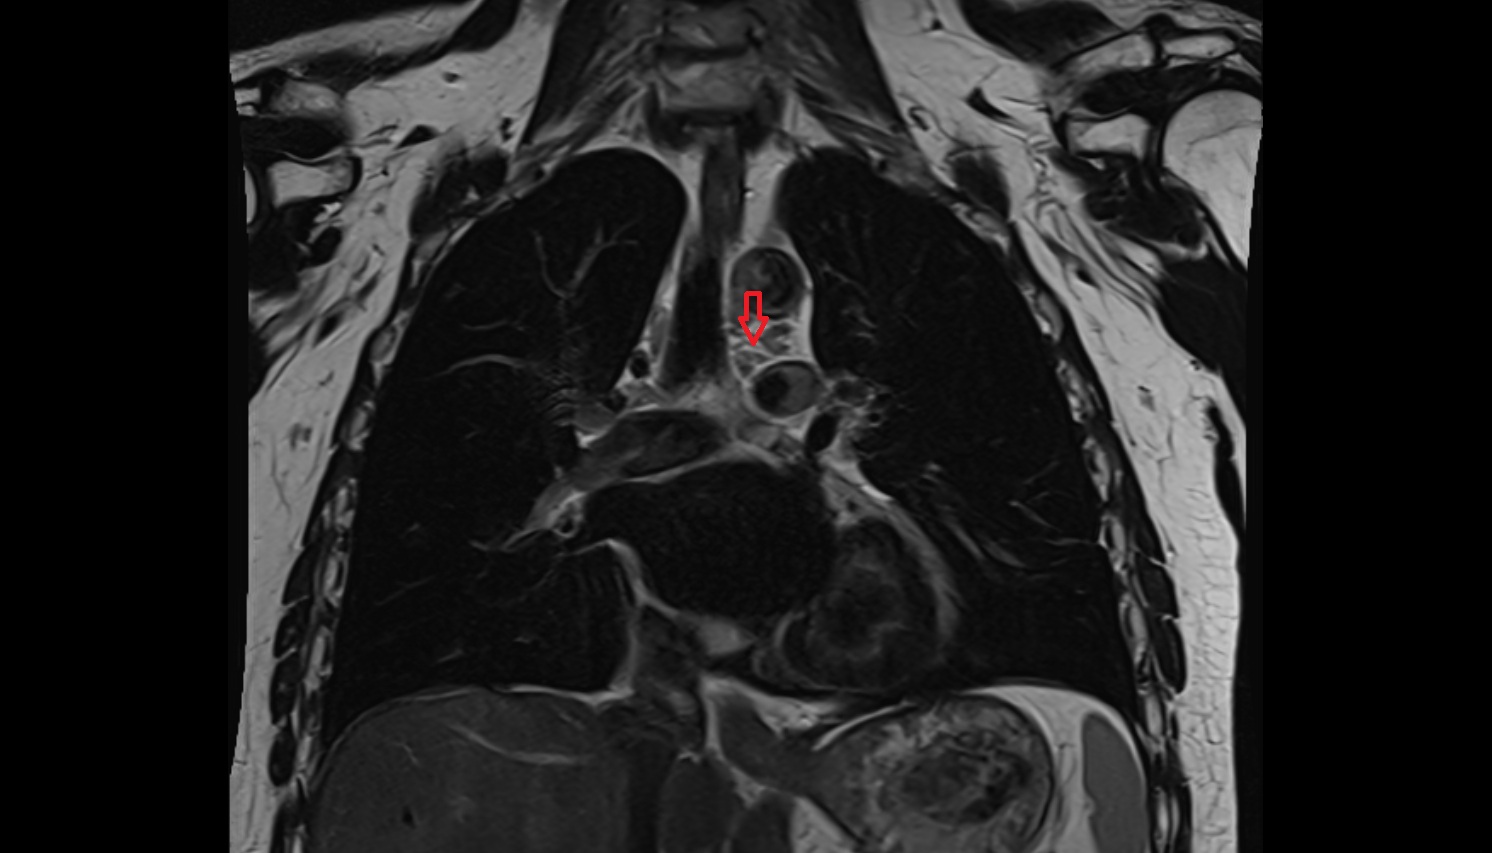

- Ascending aorta

- Arch of aorta

- Descending thoracic aorta